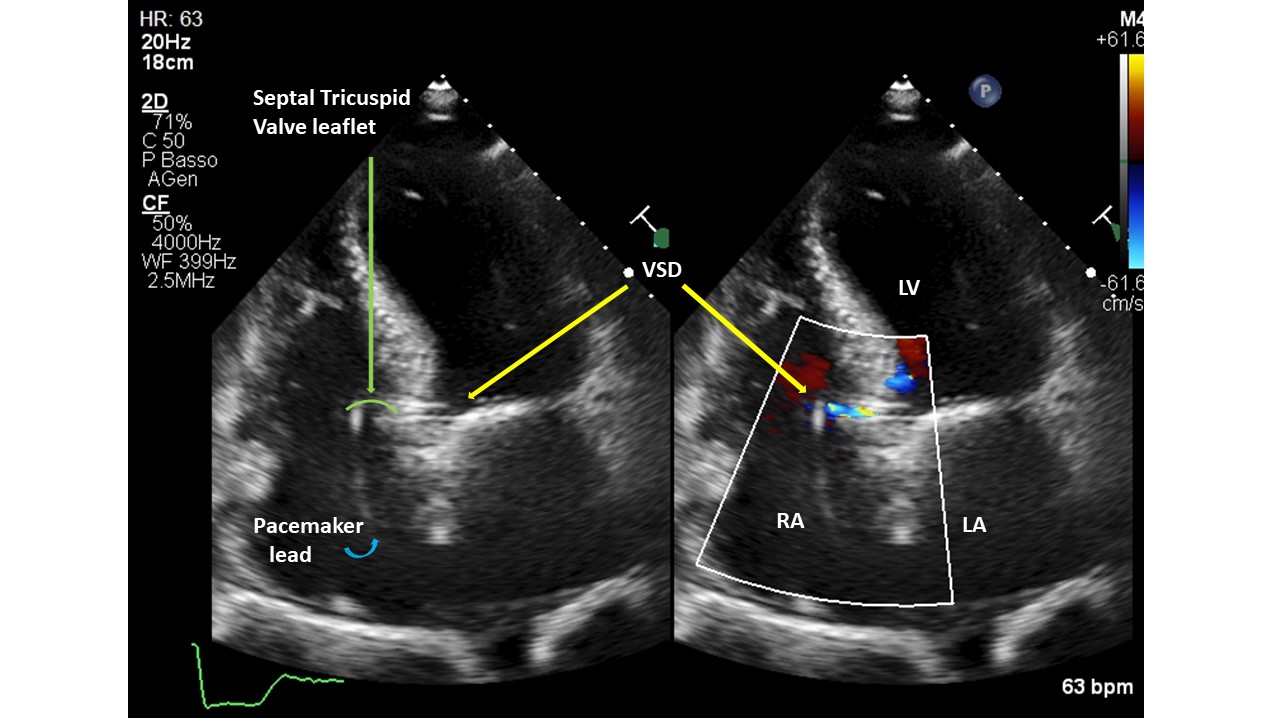

Introduction. Gerbode’s defect dates back to 1857. It generally has a congenital etiology, however very rare acquired forms have been described as complications of cardiac surgery, bacterial endocarditis, thoracic trauma, myocardial infarction or Transcatheter Aortic Valve Implant (TAVI). Diagnosing the communication between the left ventricle and the right atrium post-TAVI is not always easy, but a thorough echocardiography can lead to the correct diagnosis. We present 2 patients with Gerbode's defects post-TAVI, presumed with post-procedural transthoracic echocardiography (TTE) and validated with transesophageal (TEE) or 3D-ultrasound (3DTTE). Methods. A single-centre retrospective study of 1309 consecutive with severe aortic stenosis patients, who underwent TAVI from 2020 to 2025, was conducted with 5 types of aortic valve. All patients were evaluated with TTE before and after the procedure; only 23 patients underwent TEE. Results. Screened patients had a mean age of 82±7 years. Patients had multiple cardiac and non-cardiac comorbidities and high logistic EuroSCOREs and STS scores. Two subjects (0.15%) were found to have a Gerbode-type II septal defect. They were implanted with Medtronic Evolut FX+ valve. The calcium score of the aortic valve annulus was calculated in the 2 patients with CT (3,296 and 2,395 AU, respectively). Both prostheses were postdilated with a balloon to treat residual moderate paravalvular regurgitation. The cases were diagnosed with TEE/3DTTE to have a restrictive left to right shunt (Qp:Qs=1.4 case 1, 1.2 case 2). The patients were not symptomatic and did not require any further intervention. The mechanisms proposed for ventricular septal defect (VSD) formation: pressure exerted directly by the valve on the membranous septum, severe/asymmetric calcification of native valve, aggressive postdilatation. Conclusions. The role of TEE/3DTTE in the accurate diagnosis of these VSD suggests that it can be used as an alternative to other diagnostic tools, such as cardiac catheterization, CT and cardiac magnetic resonance imaging. Gerbode’s defect is a rare complication of TAVI and was detected more with balloon expandable valves, but can also occur with self-expanding ones. Percutaneous treatment was preferred over open cardiac surgery. Some, but not all, patients survived TAVI and VSD, and had a good prognosis for both patient groups with or without VSD closure. Careful follow-up with a dedicated team is essential in these patients.